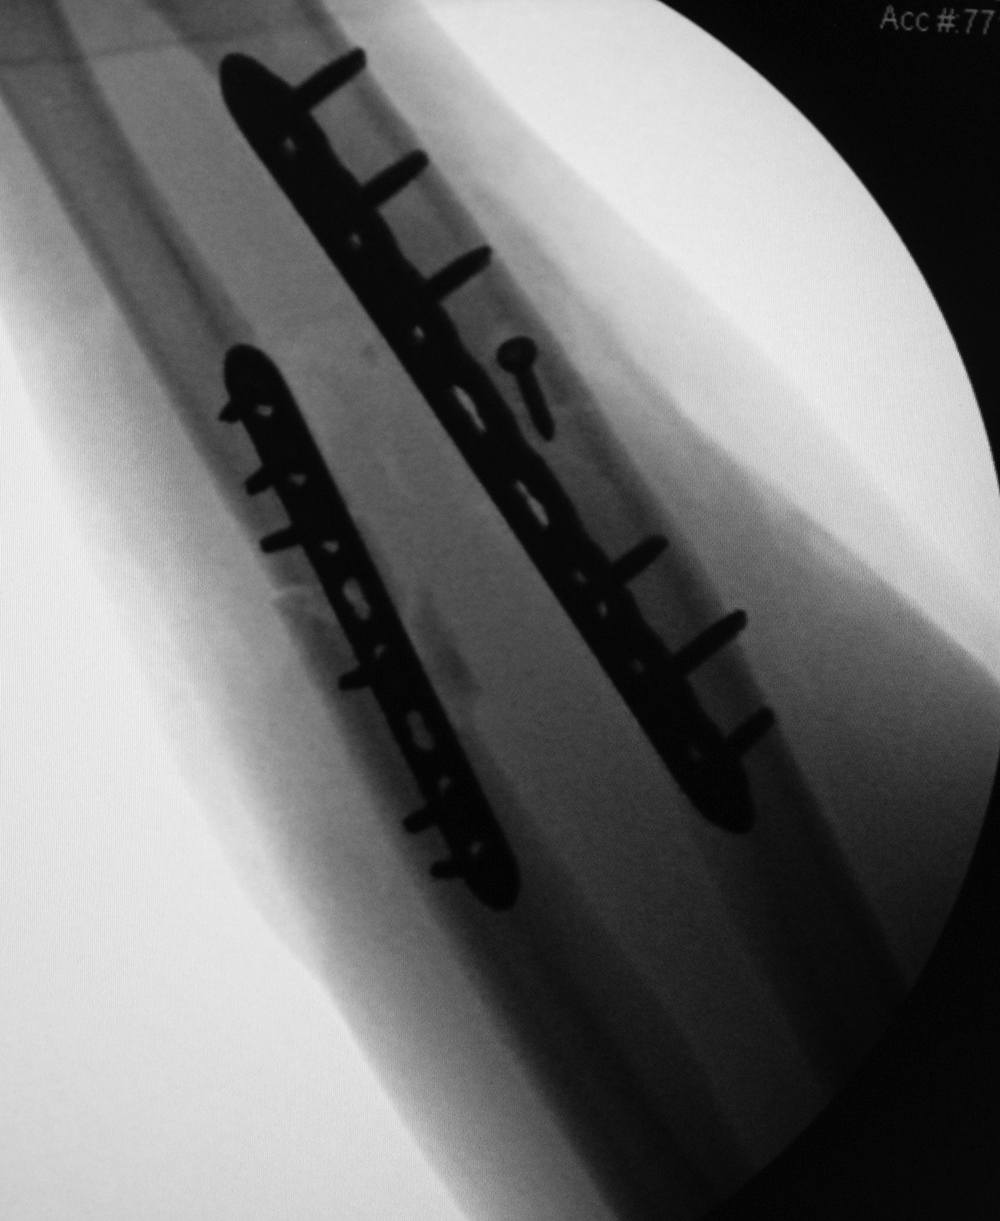

| Failure of fracture fixation due to ambulating against advice |

| Male patient with proximal tibia and fibula fractures treated by intramedullary nail and supplemental one-third tubular plate. Initial intraoperative fluoroscopic AP and lateral images (left two images) show the plate (arrow on lateral image). The patient ambulated against advice and was lost to follow-up. Two months later he again presented (right two images) to the clinic. There is now tibia fracture migration, and the proximal medial to lateral interlocking screw has backed out (AP view). The lateral view demonstrates fracture displacement with flexion deformity. The nail has troughed outside the proximal anterior tibia and is sitting within the soft tissues. The supplementary plate is broken, there is a broken interlocking screw, and abundant fracture callus is present. |